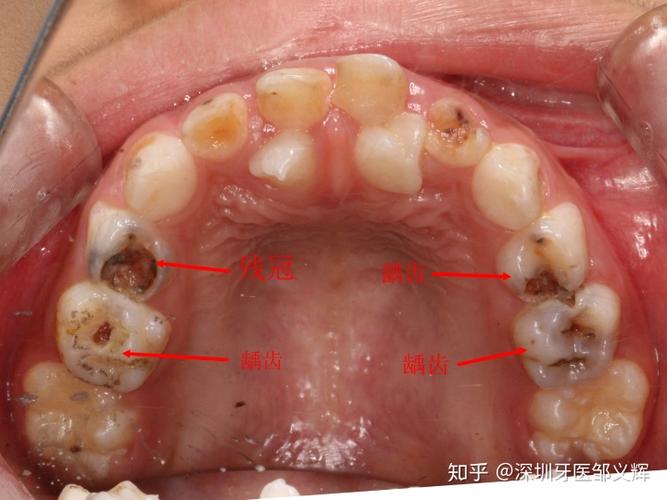

原创孩子满嘴"小黑牙",与经常吃糖无关,多半是父母无知造成的

有年轻人满口假牙的吗?我才21岁就一口坏牙很绝望,要抑郁了

7岁男童满嘴烂牙,替牙期新长的牙还不是正常的牙,我该